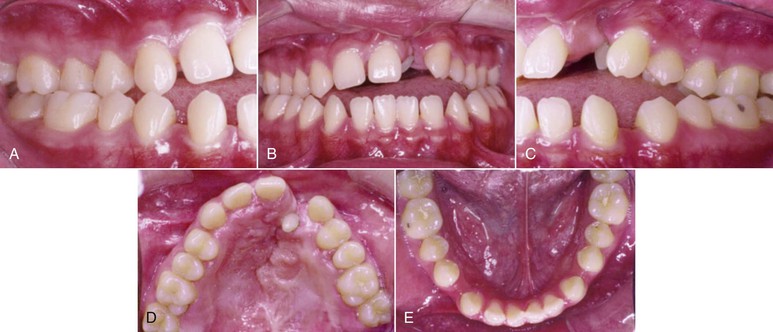

If macroglossia is diagnosed, surgical resection may be performed to reduce the volume of the tongue. The open bite can then be corrected by retraction of the anterior teeth. After treatment, stability most likely will be enhanced, because the reduced tongue volume will better match the reduced arch length obtained after retraction of the incisors (Fig. 9-11). Although this procedure may help in the reduction and stability of anterior open-bite correction, the morbidity of the procedure, with potential sequelae in taste, sensation, and motor dysfunction, explains why this approach is not often chosen.45,67

Figure 9-11 A–E, Intraoral views of a patient with a unilateral left cleft lip and palate. Significant spacing is observed in the lower arch due to a large tongue. F, Keyhole-design glossectomy. G–I, Lateral borders of the tongue to be approximated after tissue mass reduction. J, Anterior open-bite closure after surgical orthodontic treatment. K–M, Intraoral views illustrating 9-year stable result.